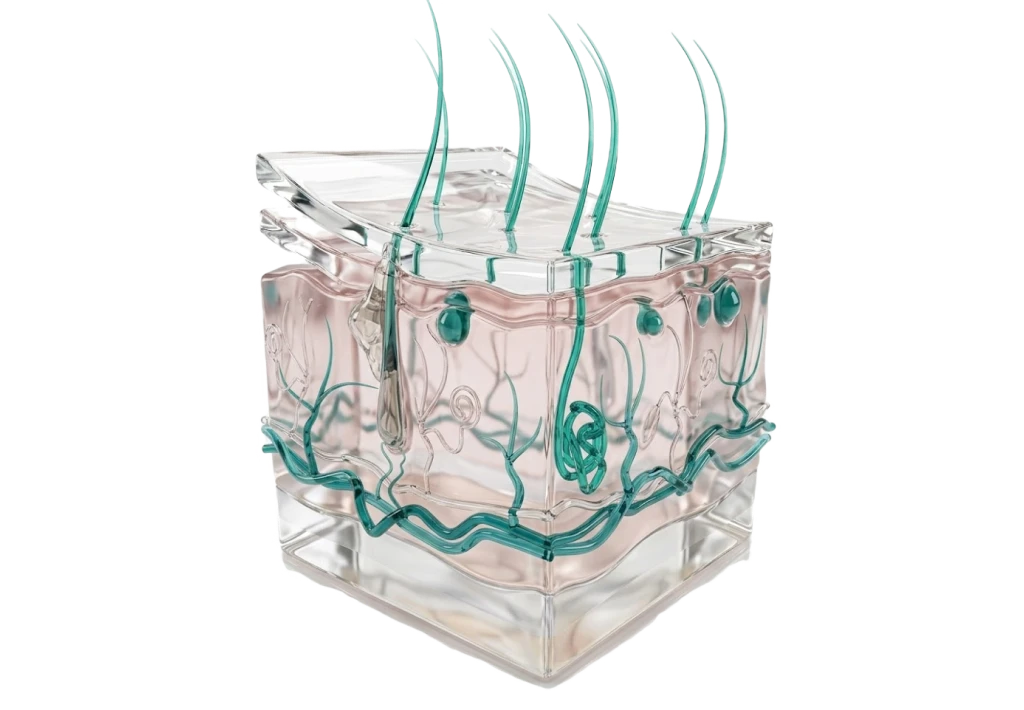

Дерматология